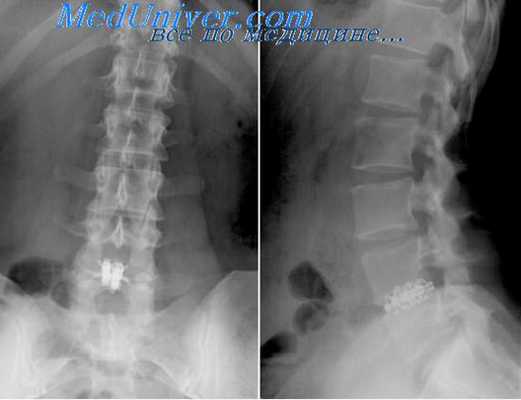

Вмешательство может успешно выполняться как под местной, так и под общей анестезией с обязательным использованием рентгеноскопического контроля. Перед операцией рентгенологически уточняется уровень патологии. После обработки операционного поля 22G иглой, вводимой на расстоянии 1,5-2 см от средней линии на уровне соответствующего межпозвоночного промежутка, рентгенологически уточняется уровень пораженного диска. Игла следует вперед в направлении нижнего края верхней пластины дуги в точку, расположенную между остистым отростком и суставным отростком.

Затем продолжается эндоскопическая диссекция тканей около позвоночника. Сегментарные сосуды (aa.lumbales и vv.lumbales) при необходимости, в зависимости от хода операции, выделяются, клипируются и пересекаются между клипсами. Это позволяет увеличить подвижность брюшной аорты и нижней полой вены, дает возможность подойти к передним и переднебоковым отделам позвонков поясничного отдела. После этого этапа визуализируются передняя поверхность межпозвоночного диска и передняя продольная связка. В диск вводится игла Steinmann и рентгенологически уточняется уровень патологии. Затем производится выделение m.psoas major с боковой поверхности позвонков.

Размер кейджа, необходимого для установки, определяется после дискэктомии и измерения образовавшейся полости между позвонками. Установка стабилизирующей системы осуществляется под прямым эндоскопическим контролем. Производится рентгенологическое подтверждение расположения кейджей в межпозвоночном промежутке.